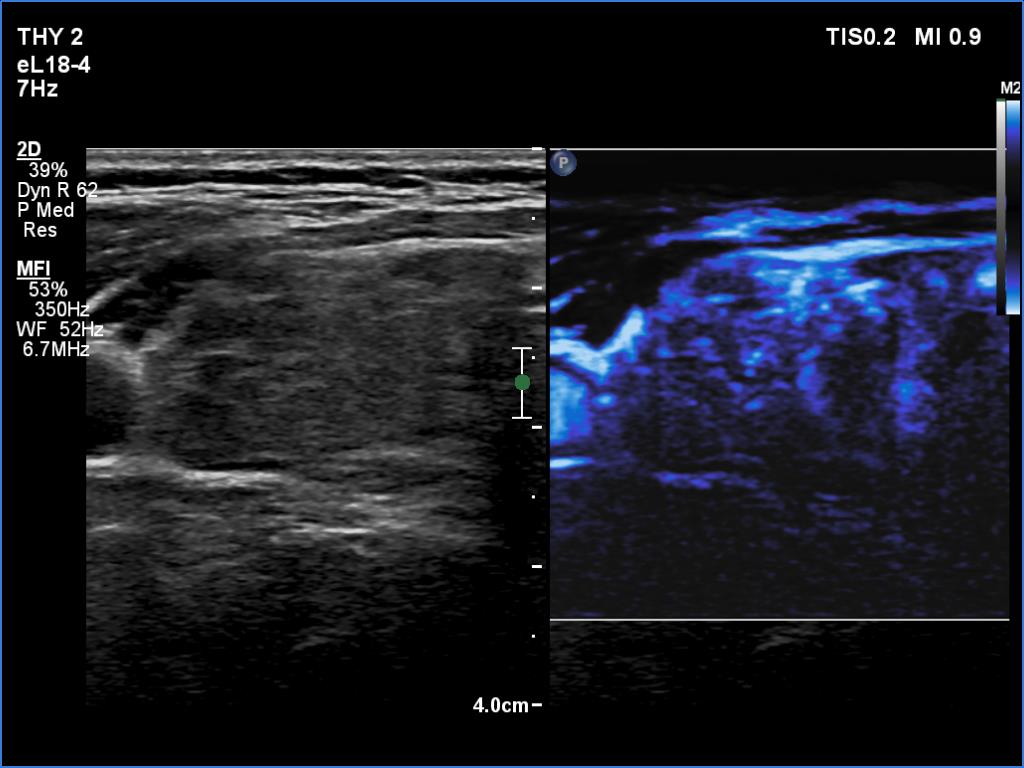

Clinical data: A 57-year-old woman was referred for evaluation of an elevated aTPO level detected on screening.

Laboratory tests: TSH 1.85 mIU/L, aTPO > 1300 U/mL.

Ultrasonography. The thyroid was minimally hypoechoic and had several discrete areas of various echogenicities. None of these lesions corresponded to true nodule.